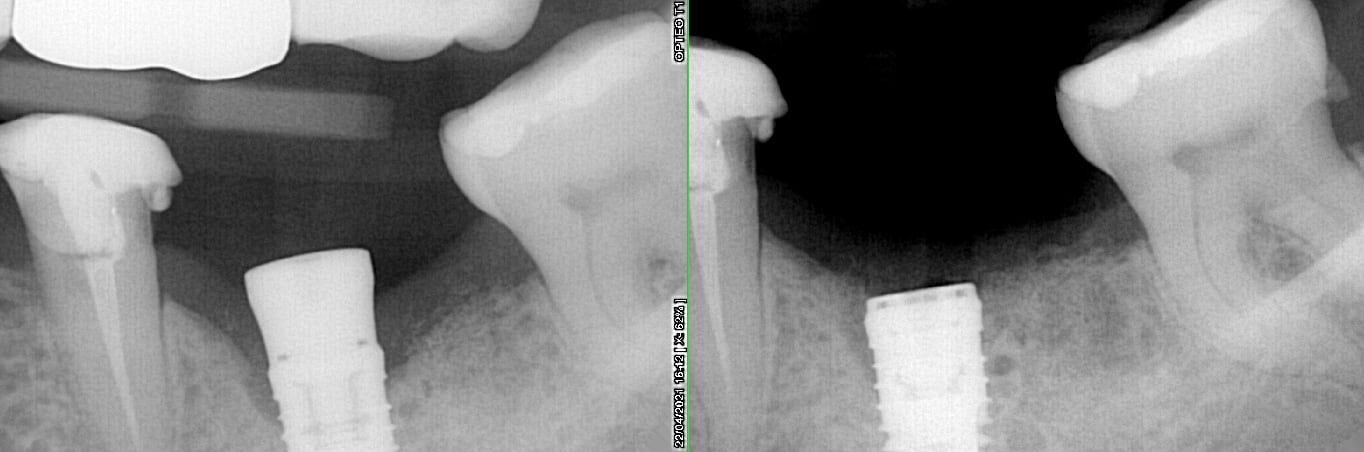

Qu'indiqueriez vous comme protocole pour traiter le début de cette cratérisation (implant posé début janvier) ? Curetage ? Laser ? Parocline ?

Moi je laisserais çà un peu tranquille avec la vis de cicat....et revoir dans quelques mois....soit c'est mieux et prothèse, soit status quo et pourquoi pas passer à la prothèse, soit çà empire...et là tourne à gauche...

les implants Xive sont assez compressifs, c'est pas forcément le meilleur implant pour un os mandibulaire...